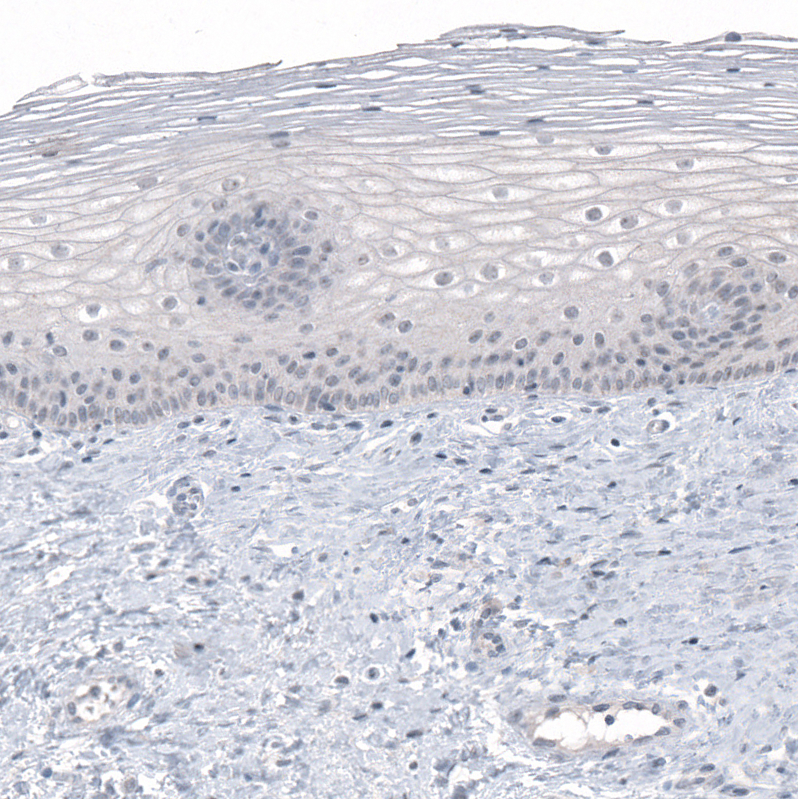

Immunohistochemistry analysis in human testis and cervix, uterine tissues using AMAb91330 antibody. Corresponding PRAME RNA-seq data are presented for the same tissues.